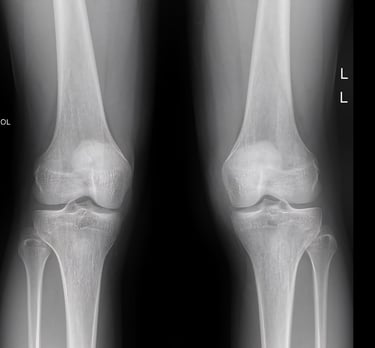

Knee X-rays

High-resolution digital imaging for knee injuries, joint pain, and orthopedic recovery tracking. We provide detailed views to assist in accurate diagnosis and Road Accident Fund (RAF) claims.